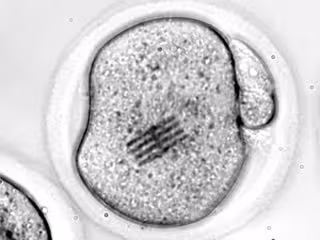

Un equipo de investigadores liderado por el Consejo Superior de Investigaciones Científicas (CSIC) en el Instituto de Microelectrónica de Barcelona (IMB-CNM-CSIC) ha fabricado unos chips que ha introducido dentro de células vivas, concretamente en óvulos, para detectar los cambios mecánicos que se producen en las etapas tempranas del desarrollo.

En su trabajo, publicado en la revista 'Nature Materials', los científicos han inyectado el chip en el interior de un óvulo de ratón junto con un espermatozoide para estudiar las etapas iniciales de la fertilización. El dispositivo, que funciona como sensor mecánico, mide apenas 22 por 10,5 micrómetros, tiene un grosor de 25 nanómetros (tres veces menor que el de un virus como el SARS-CoV-2) y una longitud 3 veces más pequeña que el diámetro de un cabello humano.

Con el chip dentro, los científicos han podido medir las fuerzas que reorganizan el interior del óvulo, es decir, su citoplasma, desde que se introduce el espermatozoide hasta que se divide en dos células. "Haciendo un símil con el baile, el embrión realiza una coreografía de movimientos durante su desarrollo y hemos visto que no solo el movimiento es importante sino también la intensidad del mismo", comenta el líder del trabajo, José Antonio Plaza, que dirige el Grupo de Micro y Nanoherramientas en el IMB-CNM-CSIC.

"Nosotros vemos a través de microscopia óptica cómo el chip se dobla en el interior de la célula". "Dado que conocemos perfectamente qué fuerza hay que aplicar para que se doble el dispositivo de una determinada manera, y lo hemos modelizado, visualizar la curvatura nos permite inferir qué fuerzas mecánicas se están dando en el interior de la célula", añade Plaza.